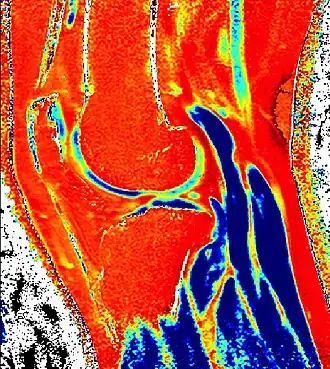

![]() dGEMRIC T1 Map of knee cartilage  | |

| Purpose | measures relative proteoglycan content of articular cartilage |

Delayed gadolinium-enhanced magnetic resonance imaging of cartilage or dGEMRIC measures the fixed-charge density and relative proteoglycan content of articular cartilage using the spin-lattice relaxation time or T1 relaxation time.[1] Current research is investigating the clinical application of dGEMRIC as a quantitative tool for monitoring cartilage function in diseased or repair cartilage.[2]